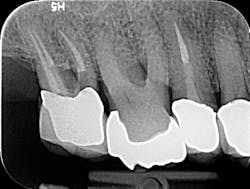

Figure 2

I then employ two instruments, the 30/02 Shaper and the 30/04 Finisher (Tango-Endo, EDS) that are also used in a 30- to 45-degree, reciprocating handpiece, but designed with a more efficient flute design to remove tissue and shave dentin away in the longer bucco-lingual isthmuses that may be present. These instruments are also highly resistant to separation, but for caution I suggest limiting their use to three teeth. Generally, there is little need to instrument the canals with larger instruments. If, in fact, the canal is wider than the instrument mesio-distally, in the same way the instruments can broaden the preparation bucco-lingually, they will also accomplish this task in the mesio-distal plane. Once shaped to these dimensions, the canal is properly sealed, flooding the canal with epoxy resin cement via a bidirectional, spiral applicator and the placement of a single Tango-Endo gutta-percha point. See figures 2 and 3 for before-and-after radiographs.